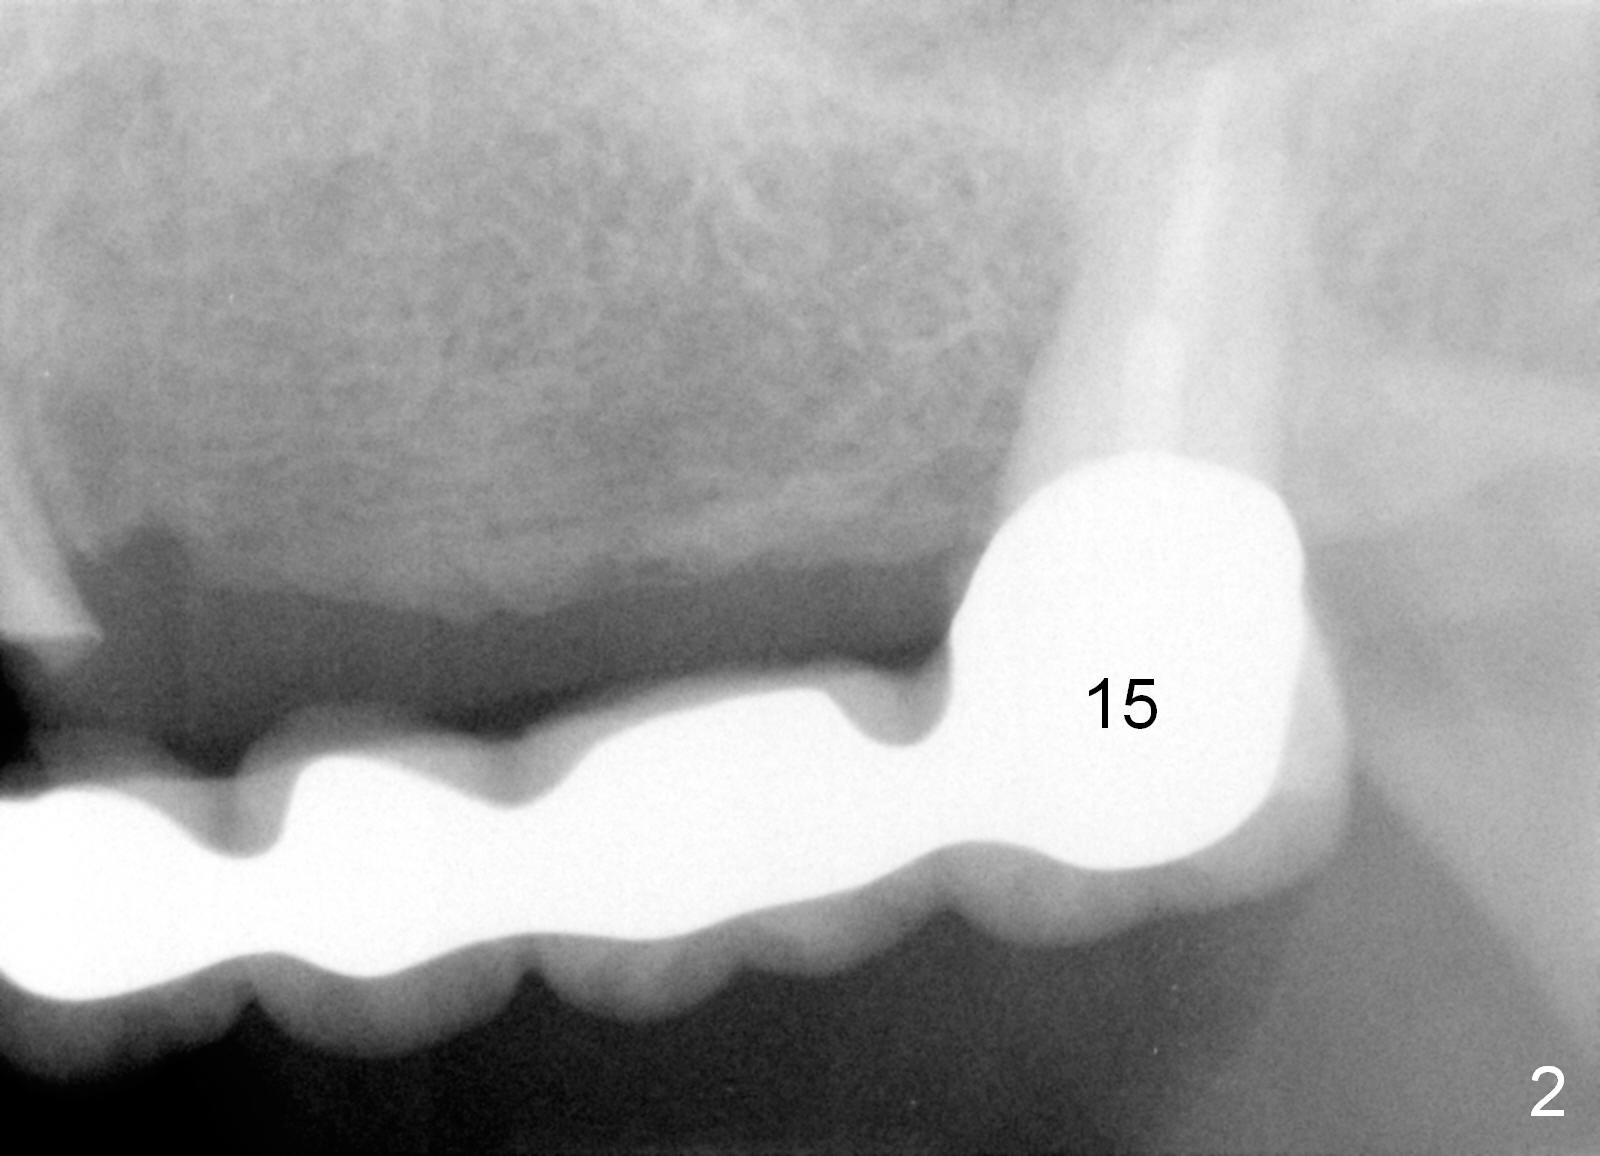

A 68-year-old female has had a long spanned FPD (fixed partial denture, bridge) for the last 2 years. It is loose (Fig.1,2). The patient is concerned about cosmetics, but has limited finance. The FPD dislodges when Alginate impression is being taken. The teeth #11 and 15 will be extracted and replaced immediately by implants (Fig.3,4). After placement of abutments, a 5-unit immediate provisional FPD will be fabricated if the implants achieve primary stability. Otherwise, an additional implant will be placed at the site of #13. There will be no occlusal contact.